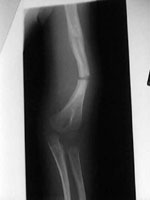

Θεσσαλονίκη: Εντυπωσιακά είναι τα επιτεύγματα πρόσθεσης ύψους σε άτομα, που πάσχουν από νανισμό (αχονδροπλασία), καθώς και για διάφορες άλλες αιτίες, με την επαναστατική μέθοδο διατατικής οστεογένεσης ή ιστογένεσης, δηλαδή της επιμήκυνσης των οστών.